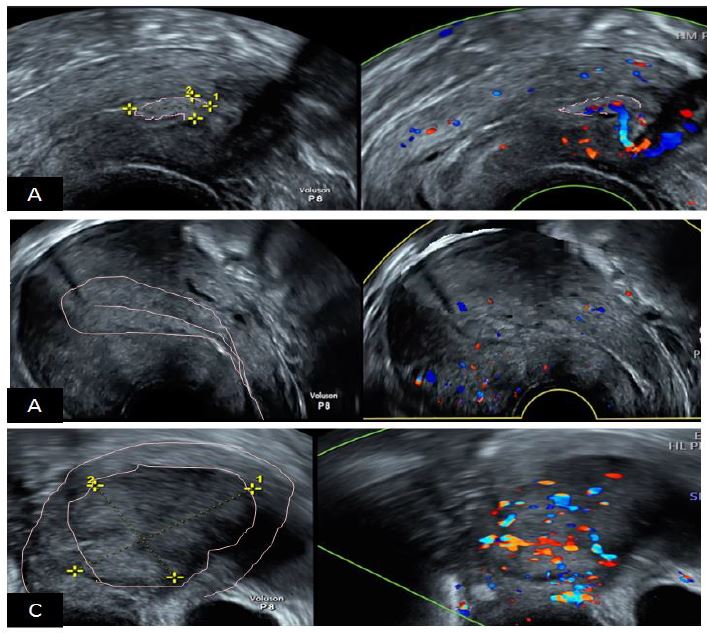

Figure 14. The International Endometrial Tumor Analysis (IETA) consensus opinion regarding the differential diagnosis between EP, EH and EM. A: endometrial polyp hyperechoic with a unique vascular pedicle; B: endometrial hyperplasia with moderate vascularization at Doppler; C: endometrial malignancy, thick image with intense hypervascularization at Doppler. Images by A. Drizi